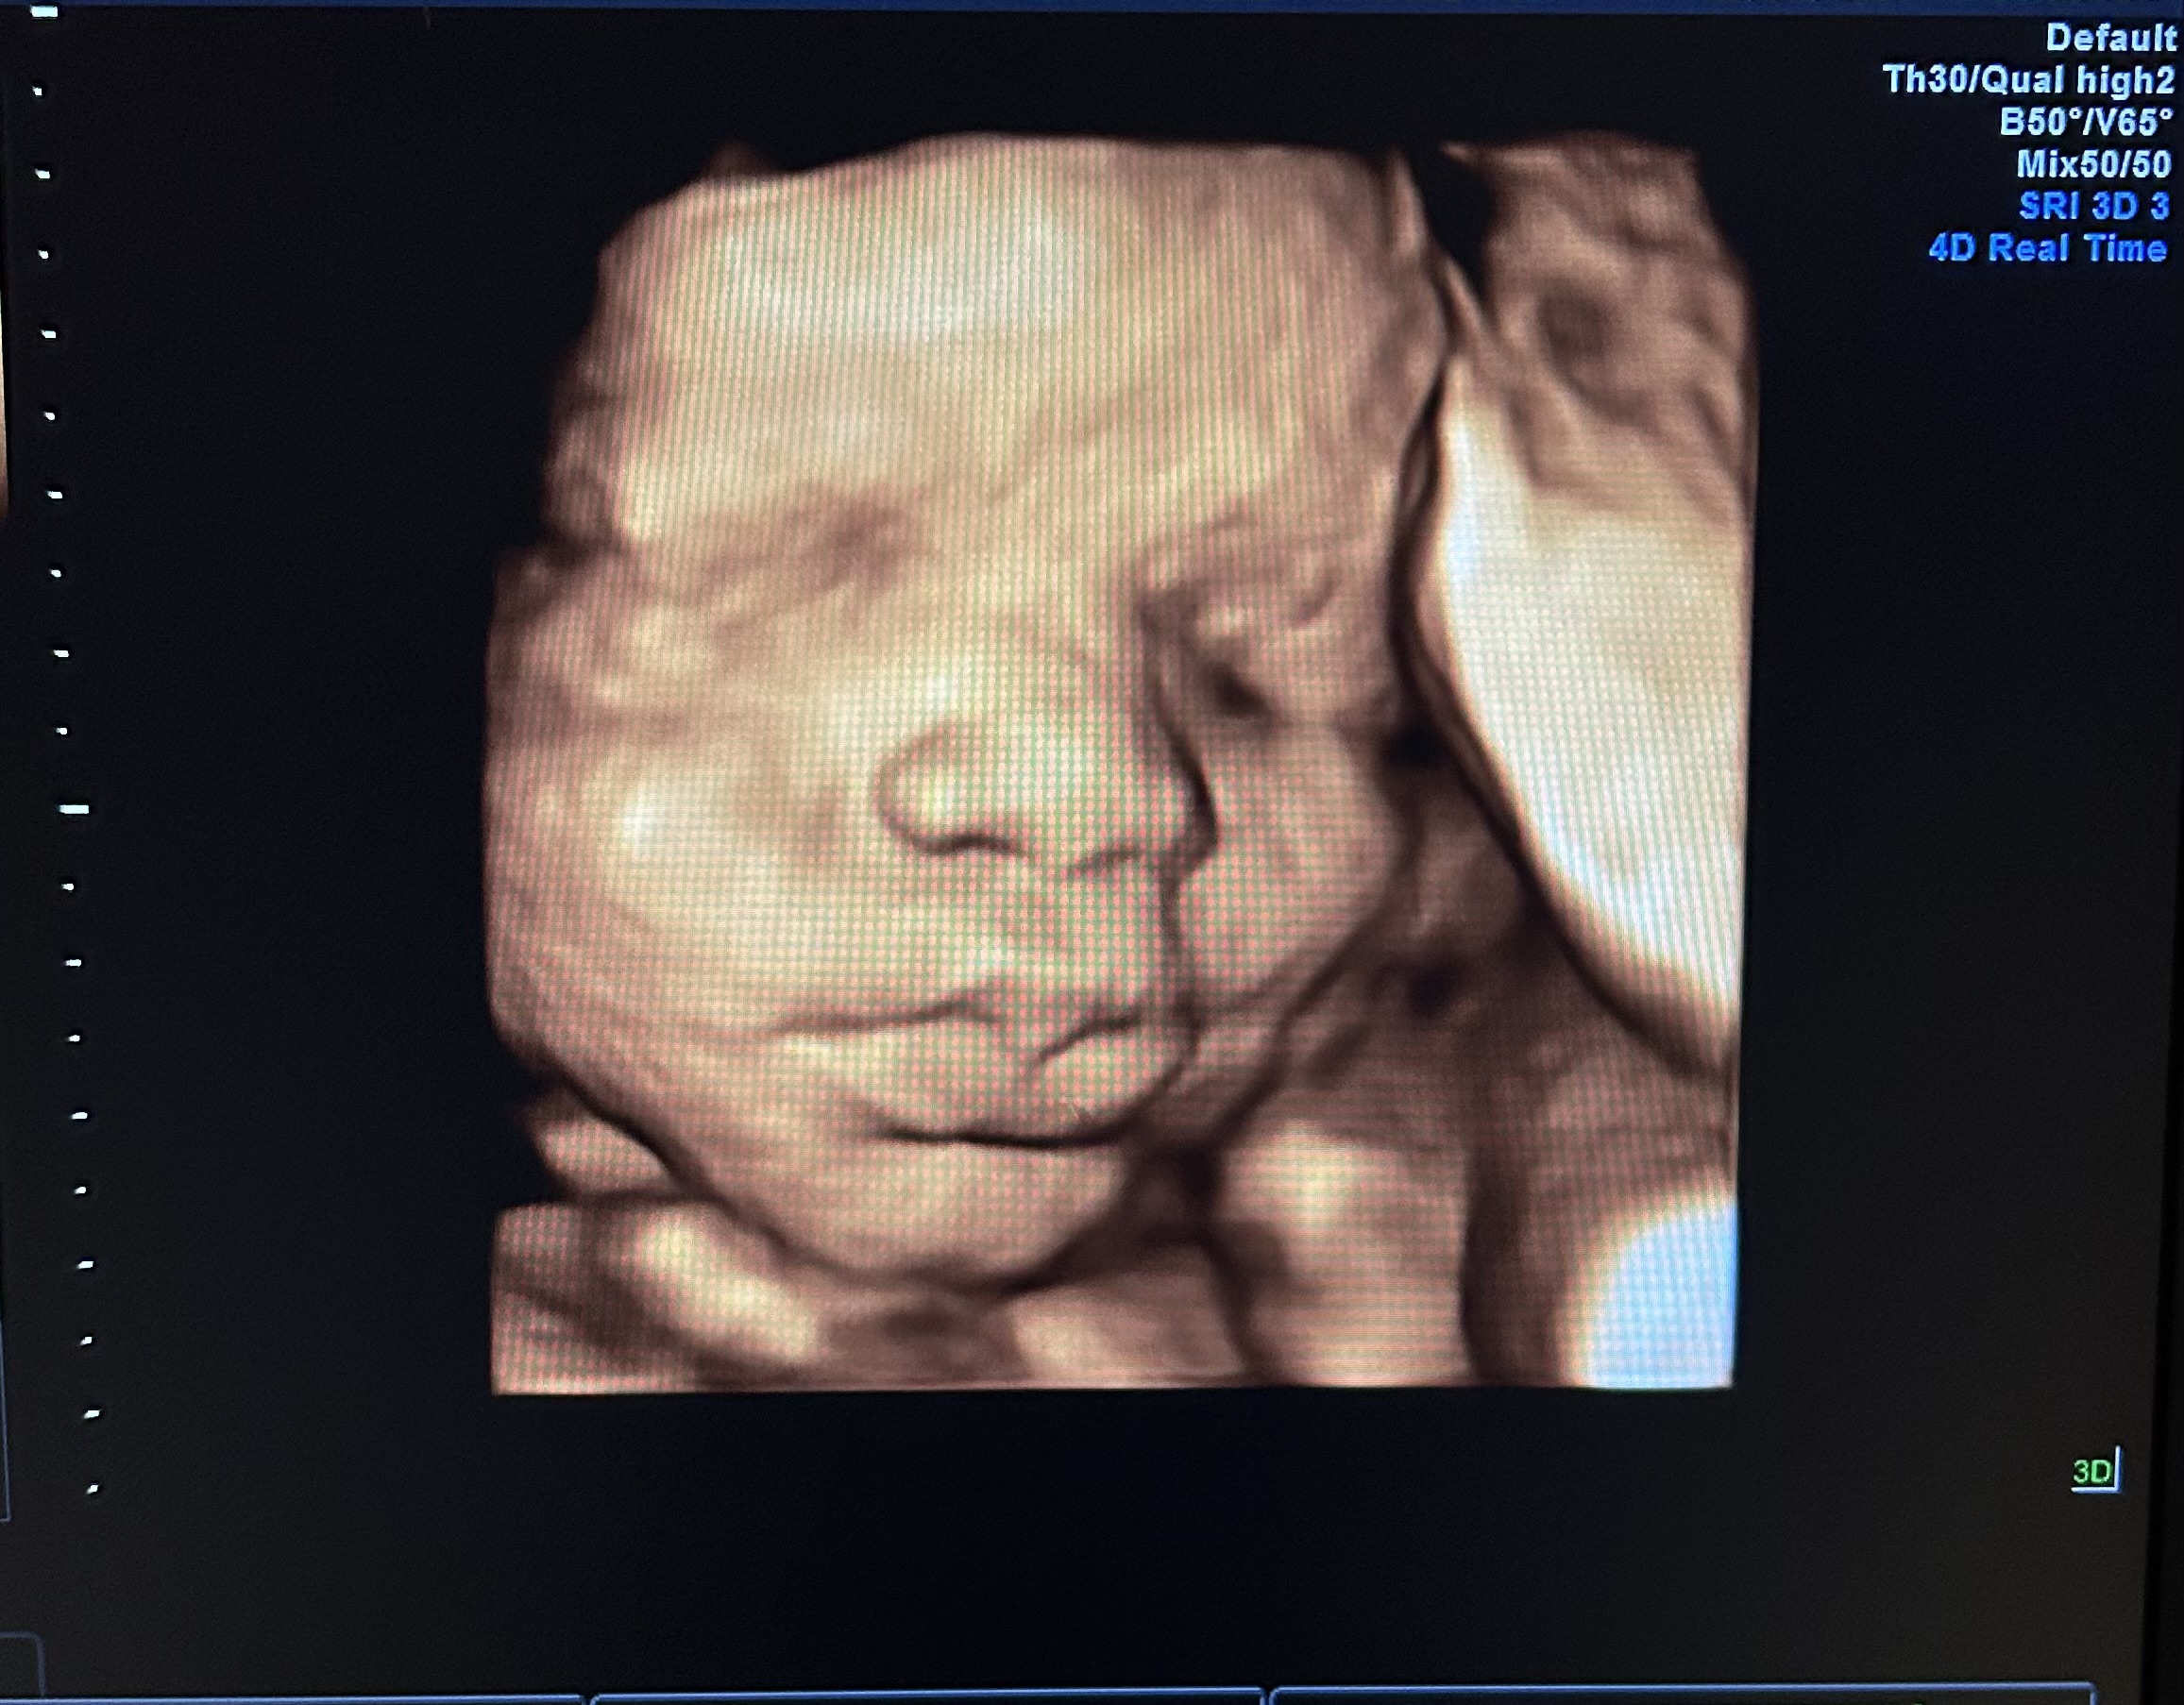

At Baby’s Image, we specialize in providing 2D, 3D, 4D, and HD live elective ultrasounds that allow families to bond with their babies long before delivery day. With nearly 18 years of experience as a registered sonographer, I bring a deep love for this profession and a commitment to creating a joyful, meaningful experience for every family who walks through our doors.

What we do goes far beyond imaging we create moments. We celebrate life. We help families experience the wonder of seeing their baby yawn, stretch, smile, or wiggle for the very first time. Those reactions the tears, the laughter, the awe are what make this work so special to us.